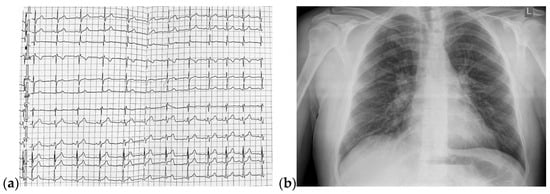

Under local anesthesia, the implantation of a single-chamber VVI mode cardiac pacemaker was carried out. The programmed HR was 55 bpm. The postprocedural ECG showed intermittent efficient ventricular paced rhythm, with HR = 57 bpm (Figure 10a). The chest radiography revealed a single-chamber pacemaker and increased vascular density in the upper half of the hilum (Figure 10b).

Figure 10.

(a) 12-lead postprocedural ECG showed intermittent efficient ventricular paced rhythm; (b) Postero-anterior chest view radiography highlighting the presence of a single-chamber pacemaker and increased vascular density in the upper half of the hilum. Abbreviations: ECG—electrocardiogram.